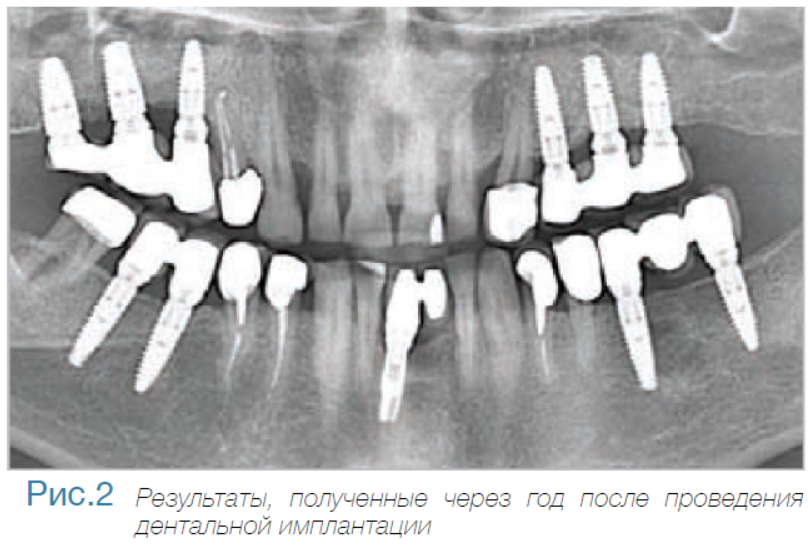

В частной практике (LS) были установлены 30 имплантатов MIS С1 (конических, с внутренним коническим соединением с переключением платформ). В исследовании приняли участие 10 мужчин и 8 женщин, при этом средний возраст пациентов составил 57 лет (возрастной диапазон 35-75 лет). 6 пациентов были курильщиками. 9 имплантатов установили на верхней челюсти, 21 – на нижней челюсти, 13 – во фронтальной области, 17 — в области боковых зубов. Для 10 имплантатов был использован одноэтапный протокол имплантации, для 20 — двухэтапный. Керамические реставрации были зафиксированы на имплантатах через 3 (18) и 6 (12) месяцев после их установки. Уровень маргинальной костной ткани с мезиальной и дистальной сторон имплантатов измерили с помощью рентгенограмм непосредственно в день установки дентальных имплантатов (исходный уровень), в день раскрытия (через 3 или 6 месяцев после установки) и ровно через год после проведения дентальной имплантации.

Ни один из имплантатов не был утрачен в течение первого года после установки, что означает 100% уровень приживаемости по прошествии года. Сокращение маргинальной кости за этот промежуток времени от имплантата до крестальной кости составило 0.7 ± 0.47 мм. Так же отсутствовала разница в сокращении уровня маргинальной кости между имплантатами, установленными по одноэтапному и двухэтапному протоколам.

Данное исследование, проведенное в частных клиниках, выявило минимальную потерю маргинальной кости, а также 100% приживаемость спустя год после установки для имплантатов С1 с коническим соединением и абатментом с переключением платформы. Результаты показали значительно большую устойчивость крестальной кости для имплантатов с коническим соединением и переключением платформ, в сравнении с имплантатами с плоскостным соединением, описанными в научной литературе.